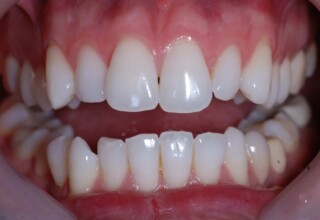

Porcelain Veneers

The best way to solve esthetic problems of the anterior teeth. They combine very little tooth grinding with very high esthetic performance. In the following extensive case anterior teeth presented with: old restorations, staining, poor shape, length and tooth –gingiva ratio. Meticulous diagnostic waxing was performed on study casts and temporary veneers were manufactured. Temporary veneers were used intraorally to evaluate the incorporated changes and to further modify and adjust were needed. When esthetics and function were approved by the patient and were satisfying for the operator the temporaries were used as a guide for the final porcelain veneers. The five final veneers on the upper anterior teeth restored the smile of the patient to almost perfection.